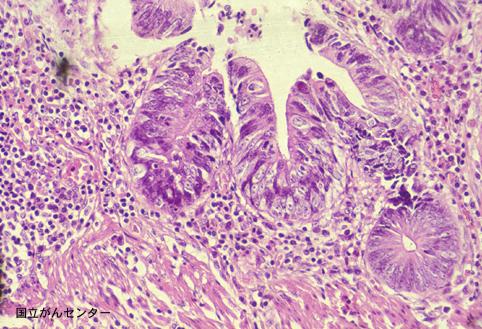

疾病(病理主体)的分类恶性上皮性肿瘤/腺癌

部位(按器官分)大肠/直肠

检查方法病理切片(微观)

肿瘤的肉眼分类0型(表在型)/IIc型(IIc)

肿瘤最大直径1~9

肿瘤的深度m